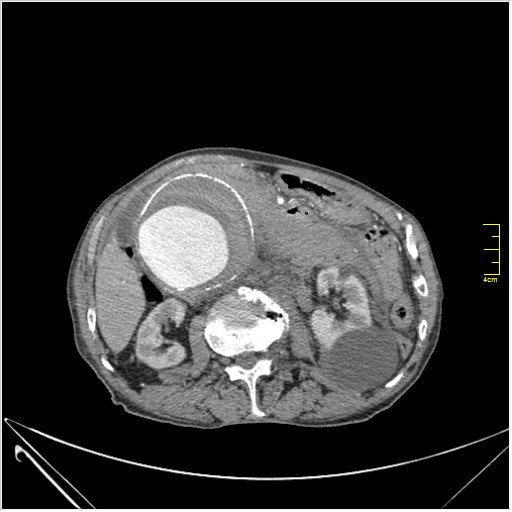

КТ брюшной полости. Мужчина с пальпируемой опухолью в животе

Пациент Т. 64 года, обратился на КТ брюшной полости амбулаторно (!), по направлению семейного врача с диагнозом abdominal mass, буквально: образование брюшной полости.

Uzgraph писал(а):Случай интересный - ногу сломишь. Вроде бы анефризма брюшной аорты(особенно по УЗИ), но что тогда за образования сидят на левой почке - онкология?

ИМХО простые кисты.